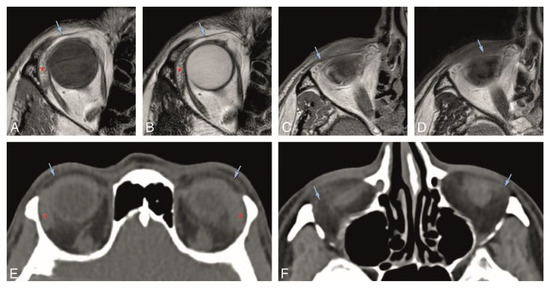

In patient #2, initially, a MRI with a standard orbit protocol was performed, followed four days later by a MRI with a dedicated eyelid protocol (Figure 6). Both showed an enhancing lesion at the medial aspect of the inferior right eyelid. With the dedicated MRI protocol invasion of the inferior tarsal plate and medial palpebral ligament region was suspected (Figure 6A–C). The relation of the tumor with the inferior tarsal plate was much more difficult to assess with the standard orbit protocol (Figure 6D–F). The medial wall of the orbit was intact on MRI. Tumor excision was performed with direct defect closure. The final histopathological examination revealed a good/moderately differentiated squamous cell carcinoma of the skin of the eyelid, with free surgical excision margins. No perineural or angioinvasive extension was found (Figure 6G,H).

Figure 6. A–H: Patient #2 of Group 3 with a SCC of the skin of the right medial inferior eyelid. Comparison between a dedicated eyelid MRI protocol with a standard orbit MRI protocol and with histopathology. A–C: Dedicated eyelid protocol with axials T1-WI (A), T2-WI (B) and contrast-enhanced T1-WI with fat signal suppression (C) at the level of the inferior eyelid, showing the tumor (blue dashed arrow) involving the medial corner of the eye, with dubious involvement of the inferior tarsal plate (yellow arrow). D–F: Standard orbit protocol with axials T1-WI (D), T2-WI (E), and contrast-enhanced T1-WI with fat signal suppression (F) at the level of the inferior eyelid. Notice the much more difficult identification of the inferior tarsal plate (yellow arrow) and its relation with the tumor (blue dashed arrow). G and H: Histopathological examination H&E stain (0.5×) (G) and histopathological examination H&E stain (5×) (H). There was no slice available containing simultaneously the tumor and the tarsal plate and, therefore, it was difficult to evaluate tarsal invasion by the tumor. Notice that on (G), the left slice includes normal tarsal plate tissue (yellow arrow), but no tumor is seen, while the right slice shows the exophytic tumor (blue dashed arrow) arising from the skin but no tarsal plate tissue is seen. Skin cell proliferation compatible with good/moderately differentiated SCC (H). Blue dashed arrow: tumor; green arrowhead: skin; yellow arrow: tarsal plate; brown arrow: conjunctiva; orange arrowhead: eyelid margin.